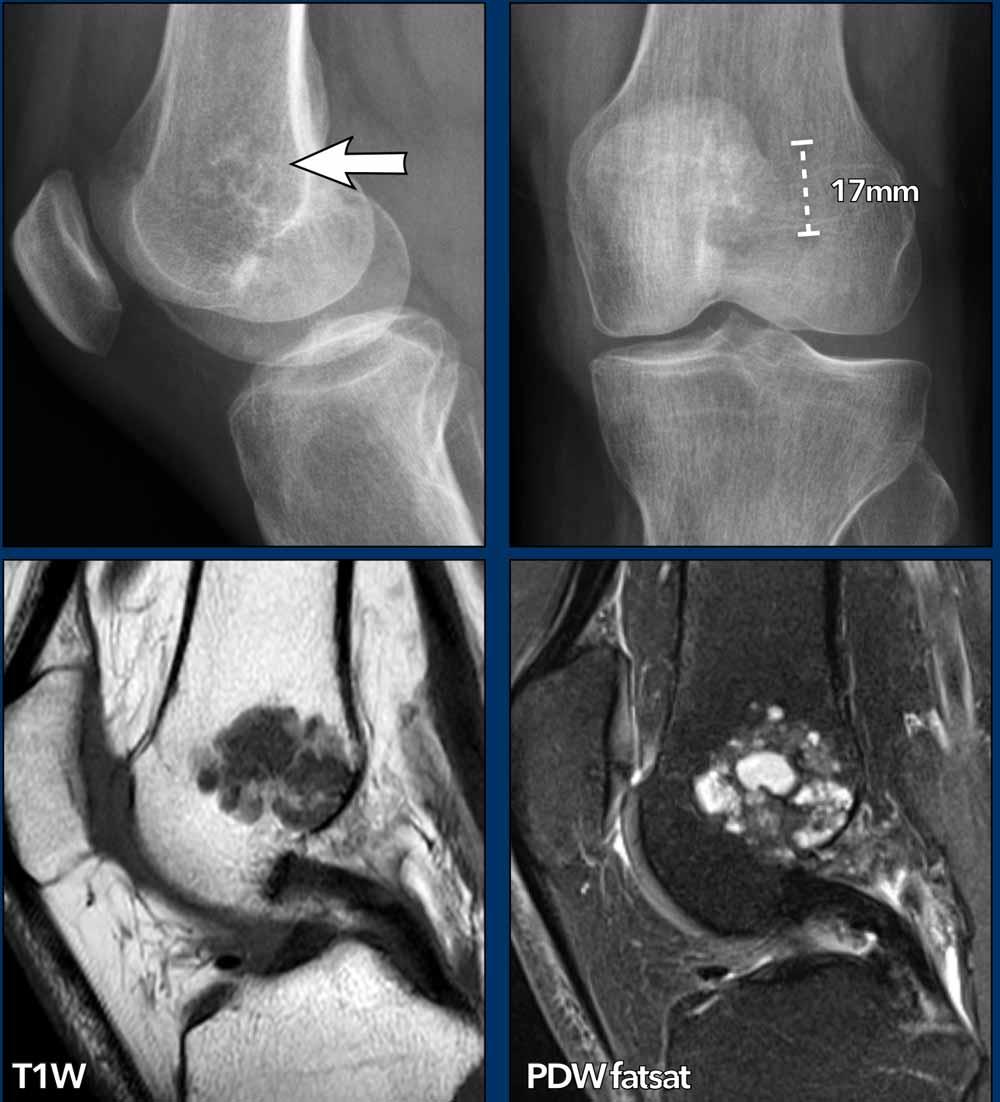

Hình ảnh

X-quang: có một vùng với các vôi hóa chất nền sụn và một số tiêu xương dưới 2 cm liền kề với sụn tăng trưởng đã đóng ở đầu xa xương đùi.

Không thấy liên quan với vỏ xương.

MRI được thực hiện để đánh giá kích thước thực sự và quyết định xem tổn thương có cần theo dõi hay không.

MRI: trên hình ảnh T1W mặt phẳng đứng dọc, tổn thương đo được tối đa 2,8 cm và có liên quan mật thiết với vỏ xương phía sau tại hõm liên lồi cầu.

Kết luận

Do tổn thương lan rộng đến vỏ não phía sau,

tổn thương được gọi là ACT và tiếp tục được theo dõi.